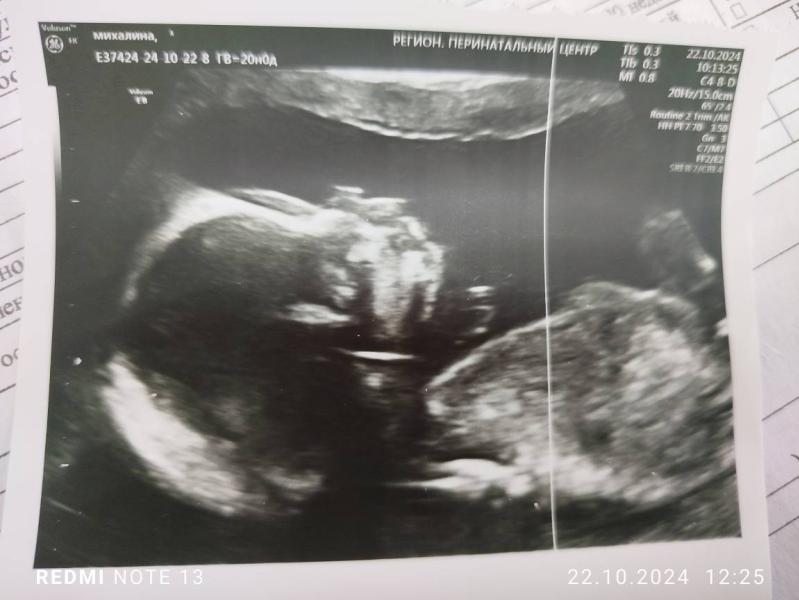

Прошли сегодня 2 скрининг) всё хорошо, поставили 20 неделек, лежим головкой вниз, пятками к верху)

Ииииии подтвердили нам, что у нас будет сыночек🥰 (узист сказала, что за сегодня не одна не пришла с девочкой, все с мальчиками😁)